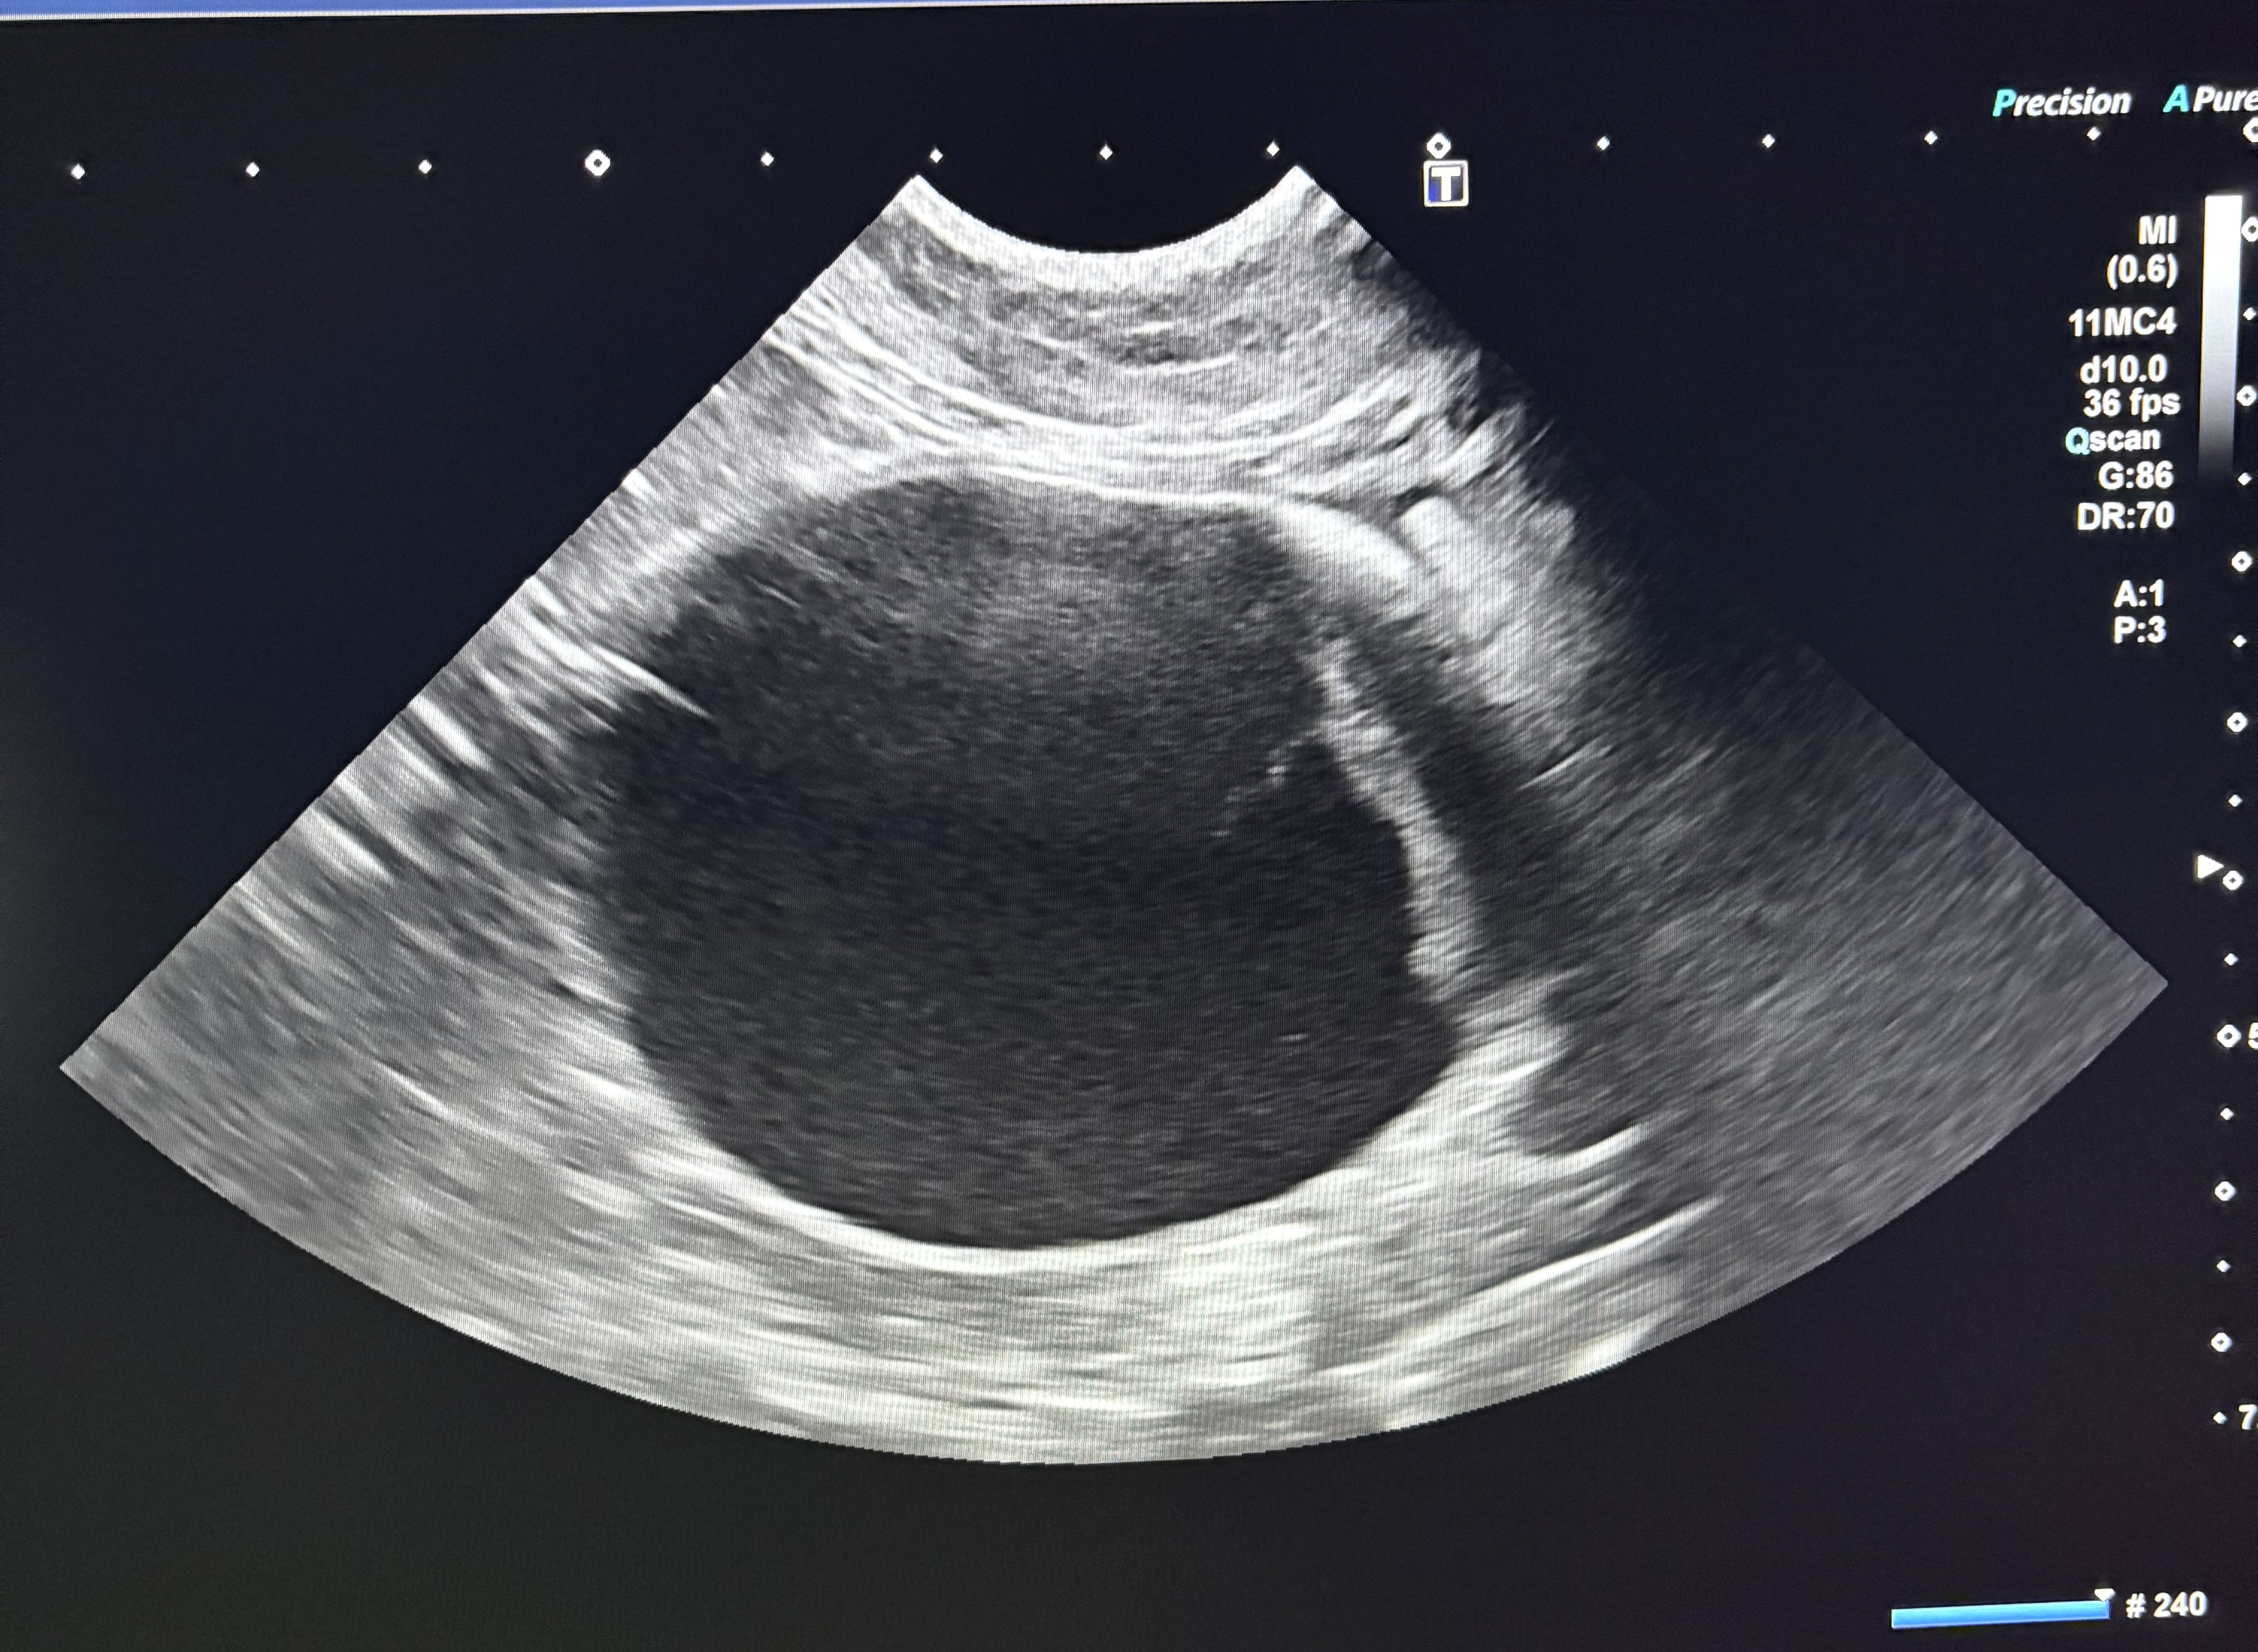

こちらは、ワンちゃんの閉塞した尿道にカテーテルを通した時のものです

よく見ると、カテーテルの中に結石がびっしりと詰まっています👀

1つ1つは小さな石ですが、細い尿道に少しずつ流れていって尿道が詰まってたり、くっついて大きな石になったりします。